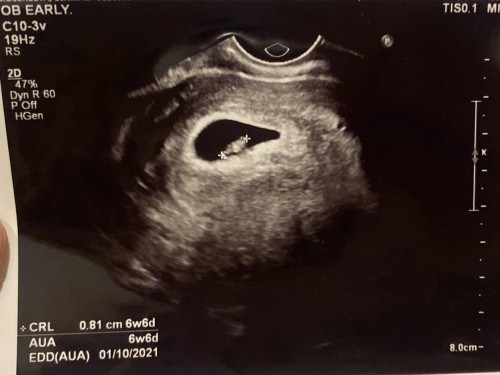

ตั้งครรภ์ 7 week

ก่อนหน้านี้ซาวด์ 5 วีค เจอแต่ถุงตั้งครรภ์ค่ะ หมอเลยนัดซาวด์อีกทีตแน 7 วีค พบน้องแล้วค่ะ มาพร้อมเสียงหัวใจเต้น หมอบอกทุกอย่างสมบูรณ์ดี ดีใจมากเลยค่ะ